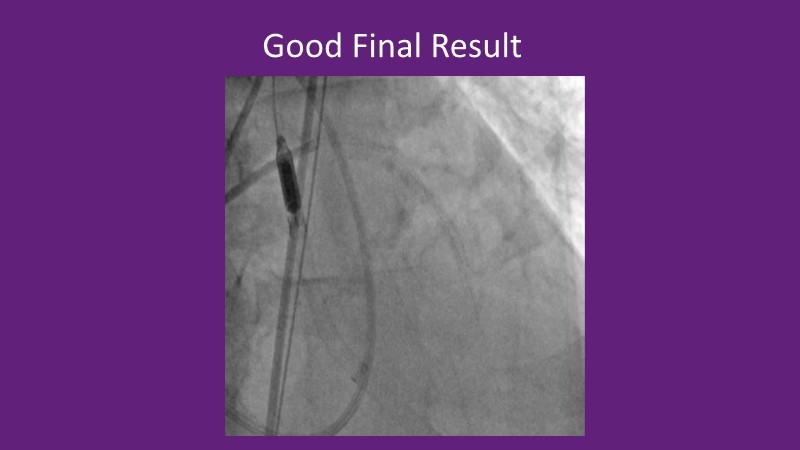

Recent data are discussed alongside insights from high-volume operators to show how calcium modification strategies are evolving and being integrated into contemporary PCI workflows.

By combining trial results, practical case experience, and emerging treatment algorithms, the discussion highlights how lesion preparation, procedural planning, and decision-making continue to improve in daily practice when managing complex calcified disease.